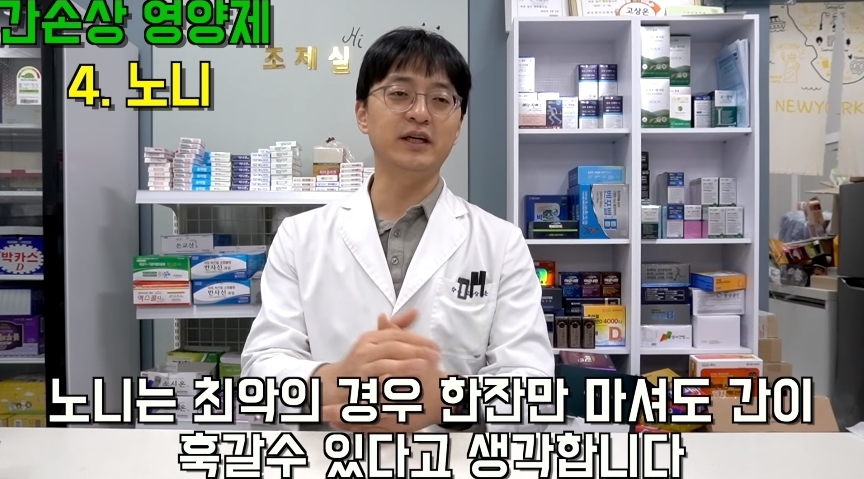

그러나 한번만 먹어도 간이 망가질 수 있다는 영양제들에 대한 글이 온라인 커뮤니티에 올라와 누리꾼들 사이에서 엄청나게 화제가 되고 있다.

해당 게시물에는 먹으면 오히려 몸에 안좋은 영양제들이 올라왔다.